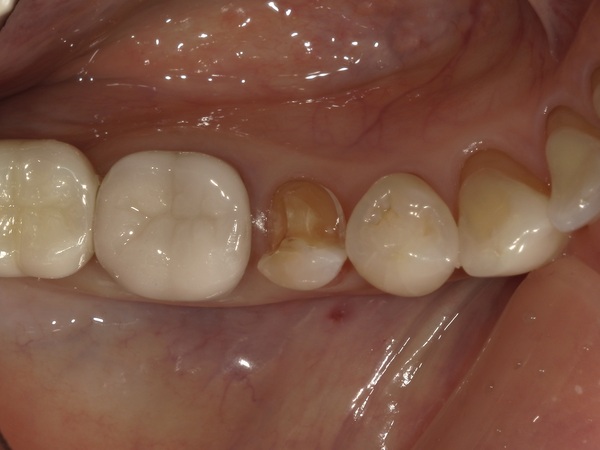

④セラミックインレーの装着

こちらが完成したセラミックインレーです。

適合・噛み合わせに問題がないことを確認し、歯科用セメントで装着しました。

治療後は不快症状もなく、経過は良好です。

お口を開けた際に気になっていた銀歯が自然な白い詰め物に変わり、患者様にも大変ご満足いただけました。